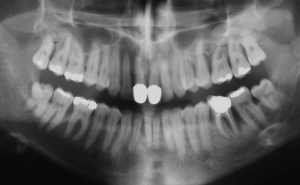

Der Erstbefund vom 20.08.1998 zeigte eine lokalisiert entzündliche marginale Gingiva mit Blutungsneigung auf Sondierung (SBI 32 %) vorrangig in regio 17, 11, 21, 24, 27, 36, 37, 41, 46. Austritt von Pus aus der Tasche an 22. Die Sondiertiefen waren durchweg erhöht, an einzelnen Parodontien konnten bis zu 12 mm sondiert werden (s. Abb. 12). Generalisiert weiche Beläge (API 46 %), harte Beläge in der UK-Front. An 41 singuläre parodontale Rezession und Zahnlockerung des Grades II, hier auch sehr schmale keratinisierte Gingiva. Mobilitätstest und Blanchingtest positiv. Der Röntgenbefund der Panoramaschichtaufnahme vom 11.08.1999 (s. Abb. 13) zeigt einen generalisierten horizontalen Knochenabbau mit vertikalen Einbrüchen in regio 17, 24, 25, 26, 36, 41 und 47. Wurzelfüllung an 36. Konkremente sichtbar. 18 elongiert. 38 und 48 halbretiniert mit Aufhellung distal.

Gemäß der 1999 gültigen Nomenklatur wurde die Diagnose Parodontitis marginalis profunda, V.a. auf RPP (Rapid Progressive Periodontitis) gestellt. Weitere Diagnose: Singuläre parodontale Rezession mit mukogingivaler Störung an 41.

a) Initialbehandlung vom 20.08. – 16.12.1999:

Gemäß den Vorgaben der systematischen Parodontalbehandlung wurden zunächst mehrfache professionelle Zahnreinigungen mit Anleitung des Patienten zu einer effizienten häuslichen Mundhygiene durchgeführt. Im Anschluss daran wurden die erkrankten Parodontien einem subgingivalen Scaling/Rootplaning unterzogen. Die Zähne 26 und 36 wurden als nicht erhaltungswürdig beurteilt und entfernt.